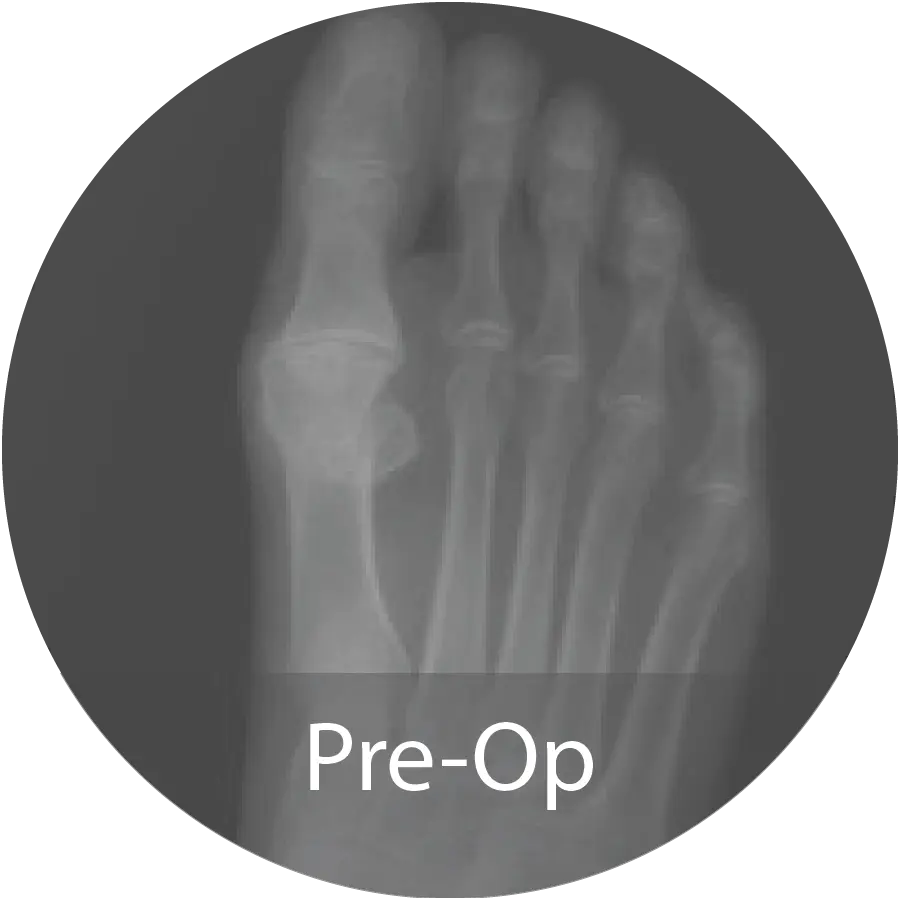

Case of 74-year-old female with hallux rigidus and multiple metallic allergies treated with 1st MTPJ arthrodesis using biointegrative hardware and InduceXT® hydrated with normal saline. Reported complete osseous consolidation at 12 months and pain-free outcome.